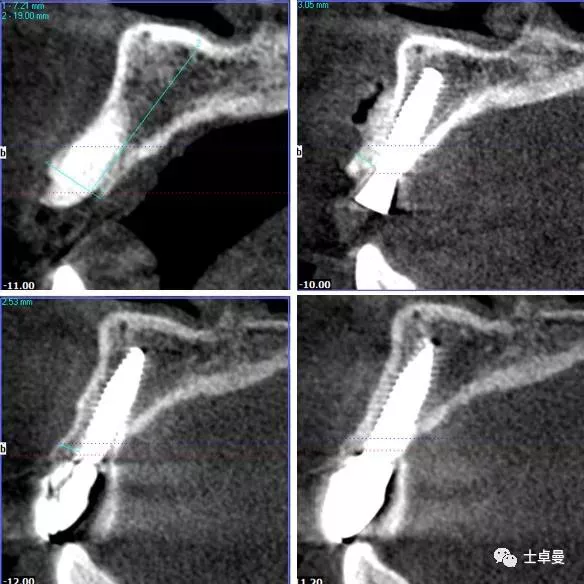

·       跳跃间隙大于2mm,跳跃间隙内放置骨粉;

偏腭侧植骨种植体

唇侧骨板下1mm

唇侧跳跃间隙大于2mm

·        CBCT显示种植体三维位置良好;

术后 CBCT 显示种植体三维位置良好

术后一年的CBCT

术后三年的CBCT

不同时期CBCT截图